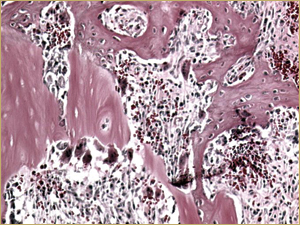

Figure 3b: High-power histologic examination of rabbit maxillary sinus augmented with autogenous bone graft at 2 weeks after grafting. H&E stain, 200× magnification.

After 2 weeks, grafted mature cortical bone fragments were present in the rabbit maxillary sinuses augmented with autogenous bone grafts (Fig. 3a). Few lacunae within the grafted bone were occupied by osteocytes (Fig. 3b). The margins of the grafted particles demonstrated active bone turnover and remodelling. Resorption of the grafted mature cortical bone was coupled with areas of newly formed woven bone. The new bony regenerate demonstrated plump osteocytes and osteoblasts.